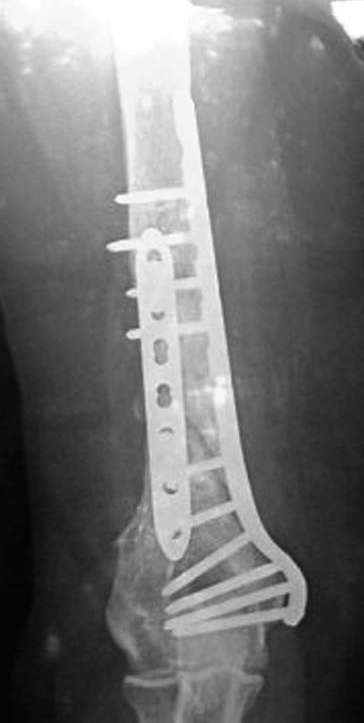

На примере два случая, извиняюсь за качество снимков, снимки и случаи из бывшего союза.

Первая больная с "успехом" была прооперирована 6 раз различными методами открытого и закрытого

остеосинтеза, включая то, что в Кисловодске заезжим австралийским "кудесником" на ложный сустав уложена скорлупа от страусиновых яиц. Последняя операция одиноким локинг плейт в одной из клиник.

Через год по поводу тех же проблем сделали ревизию, оригинальную пластину оставили как есть, только укрепили добавлением еще одной пластины и сделали костную пластику.

Через два месяца увидели признаки консолидации.